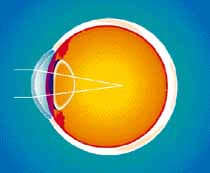

Focus problem in a nearsighted (myopic) eye |